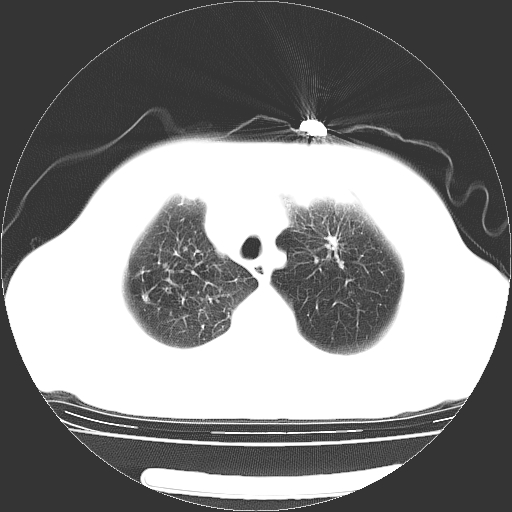

标题: CT23067:女,70岁,咳嗽、咳痰一个月,低热一周。 [打印本页]

女,70岁,咳嗽、咳痰一个月,低热一周。

1.左上肺结核,部分纤维化。右肺中下叶部分肺不张,内见液化、坏死及点状钙化,右中下叶支气管壁增厚、管腔狭窄,见多个点状钙化,结合临床考虑支气管内膜结核,建议痰检查抗酸杆菌并参考血沉。两肺多个小圆点状高密度灶,境界模糊,多考虑结核肺内播散。但本人年龄较大首先应支气管镜检以除外右肺癌。

1、右肺占位,考虑周围型ca 。

2、右下肺软组织密度肿块影,考虑肺隔离征。

3、两肺肺结核(右肺下叶背段及左肺)。

4、主动脉夹层。